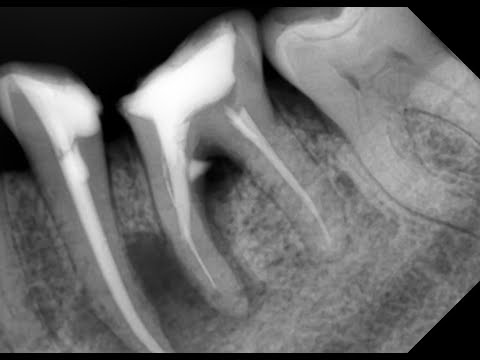

Периодонтит - вторичная эндодонтия и деструкция в бифуркации - перелечивание корневых каналов зуба

Разбор клинического случая от лекторов учебного центра Авиценна

Лечение перфорации в области фуркации корня. Лечение периодонтита. Курсы по стоматологии